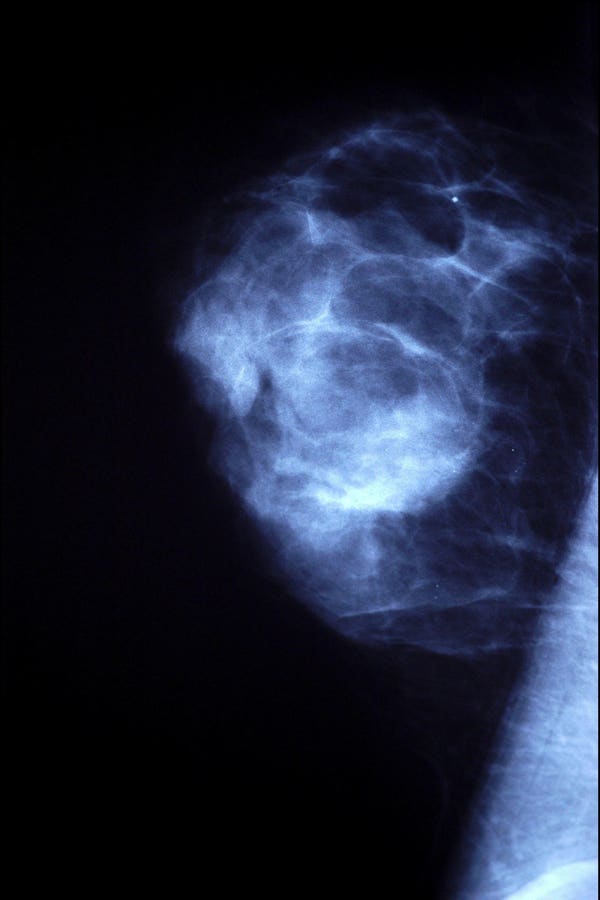

Both men and women usually undergo the same diagnostic tests when trying to identify breast cancer. For example, men or women who feel a lump in their breast will usually go on to get a mammogram, which are low-dose x-ray images geared toward detecting any abnormalities in the breast such as suspicious masses or lesions.

If an abnormality is present on a mammogram, additional studies and procedures could include an ultrasound, MRI or even a biopsy to confirm a specific diagnosis.